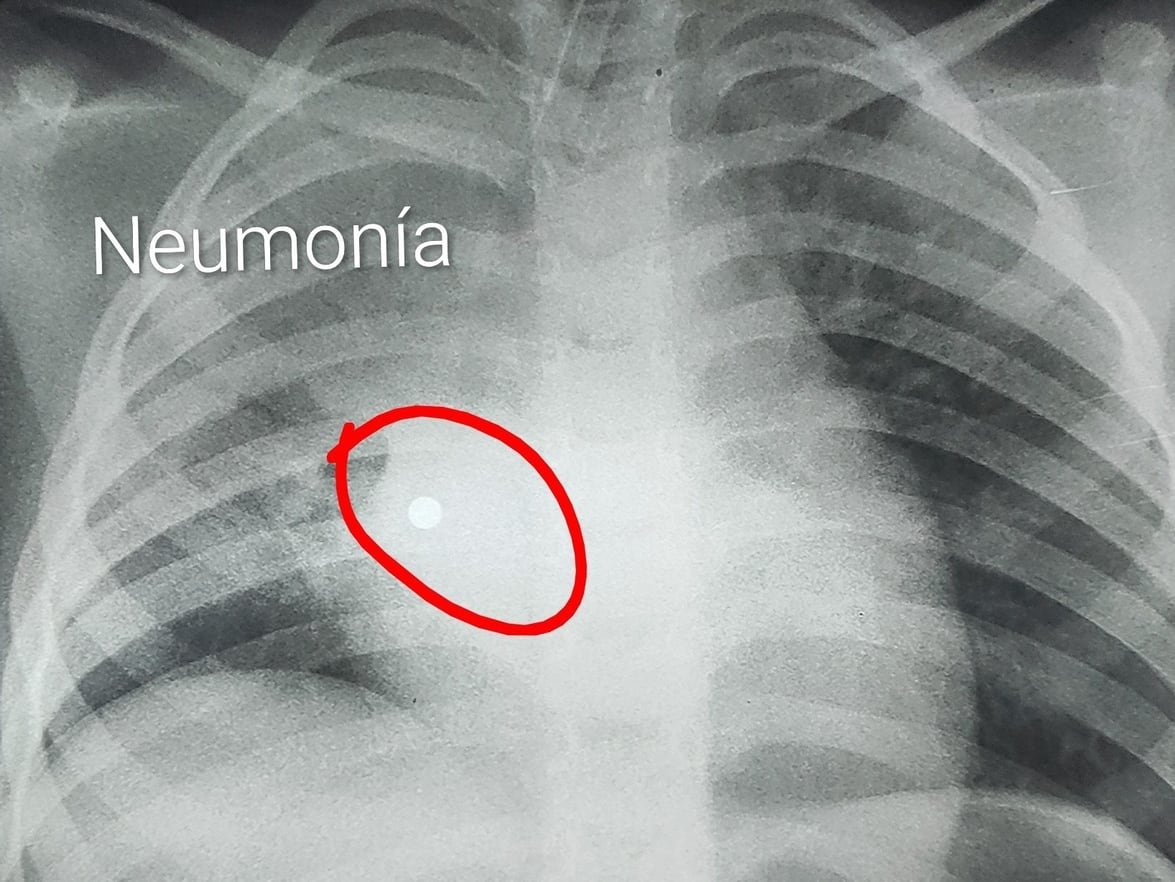

Morínigo explicó que el accidente ocurrió de manera repentina. “Una niña de cuatro años de Capiatá, agarró un souvenir, estos imanes que están por la heladera, que tenía un hilito con perlitas de metal. En un segundo mete en la boca, estira, muerde y suelta las perlas en la boca. Afortunadamente, cuatro de las perlitas fueron al aparato digestivo y una fue al pulmón. No se imaginan la catástrofe que ocasionó en el pulmón. Se paseó por todo el pulmón derecho, ocasionando obstrucción y neumonía”, relató en charla con la radio 1080 AM.

La niña fue trasladada primero a un hospital y luego al área de trauma, donde se decidió su derivación al INERAM. El procedimiento se realizó en condiciones críticas. “Aquí en hora de la siesta logramos quitar la perlita, porque estaba metida allá en el fondo del lóbulo inferior derecho”, indicó el médico interviniente.